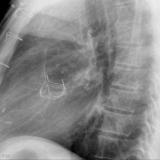

Cardiomegaly, esp RA Lat

Date: 01/26/2009

Views: 3037